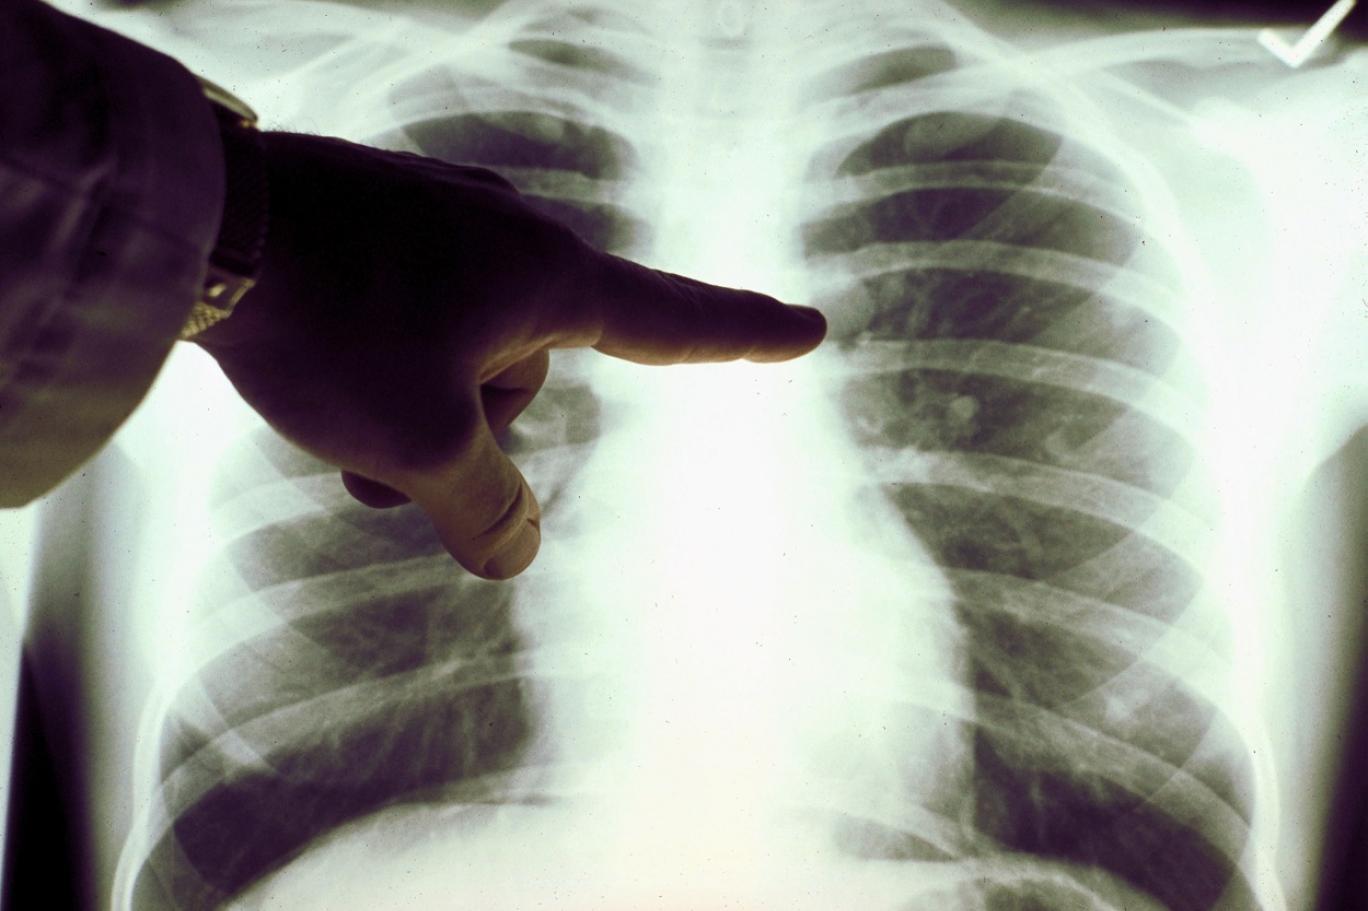

كيف يمكن لحبة دواء سرطان الرئة تقليل خطر وفاة المرضى إلى النصف؟

وجدت دراسة أن حبة سرطان الرئة التي يحصل عليها مرضى أورام الرئة في بريطانيا تقلل إلى النصف خطر الوفاة خلال 5 سنوات من العلاج.

أورام الرئة

أورام الرئة هي السبب الرئيسي لوفيات السرطان في المملكة المتحدة، مع 49 ألف حالة سنويا.

يعد سرطان الرئة أحد أكثر أنواع السرطان شيوعًا وخطورة.